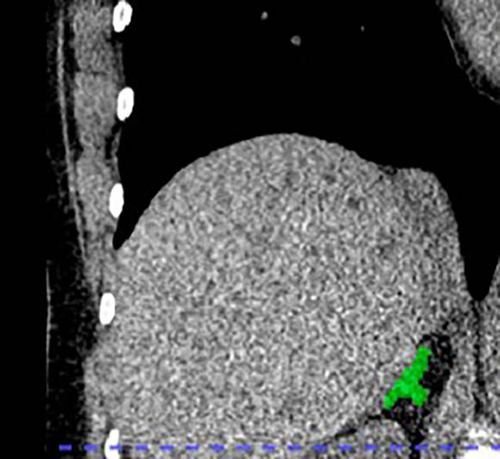

Figure 3. Right adrenal automated 2D segmentation in chest CT.

The researchers retrospectively applied their deep learning model to the CT scans to segment and calculate the volume of the adrenal glands. Adrenal Volume Index (AVI) was defined as volume (cm³) divided by height² (m²). Salivary cortisol was collected eight times per day over two days. Allostatic load was based on body mass index, creatinine, hemoglobin, albumin, glucose, white blood count, heart rate and blood pressure.